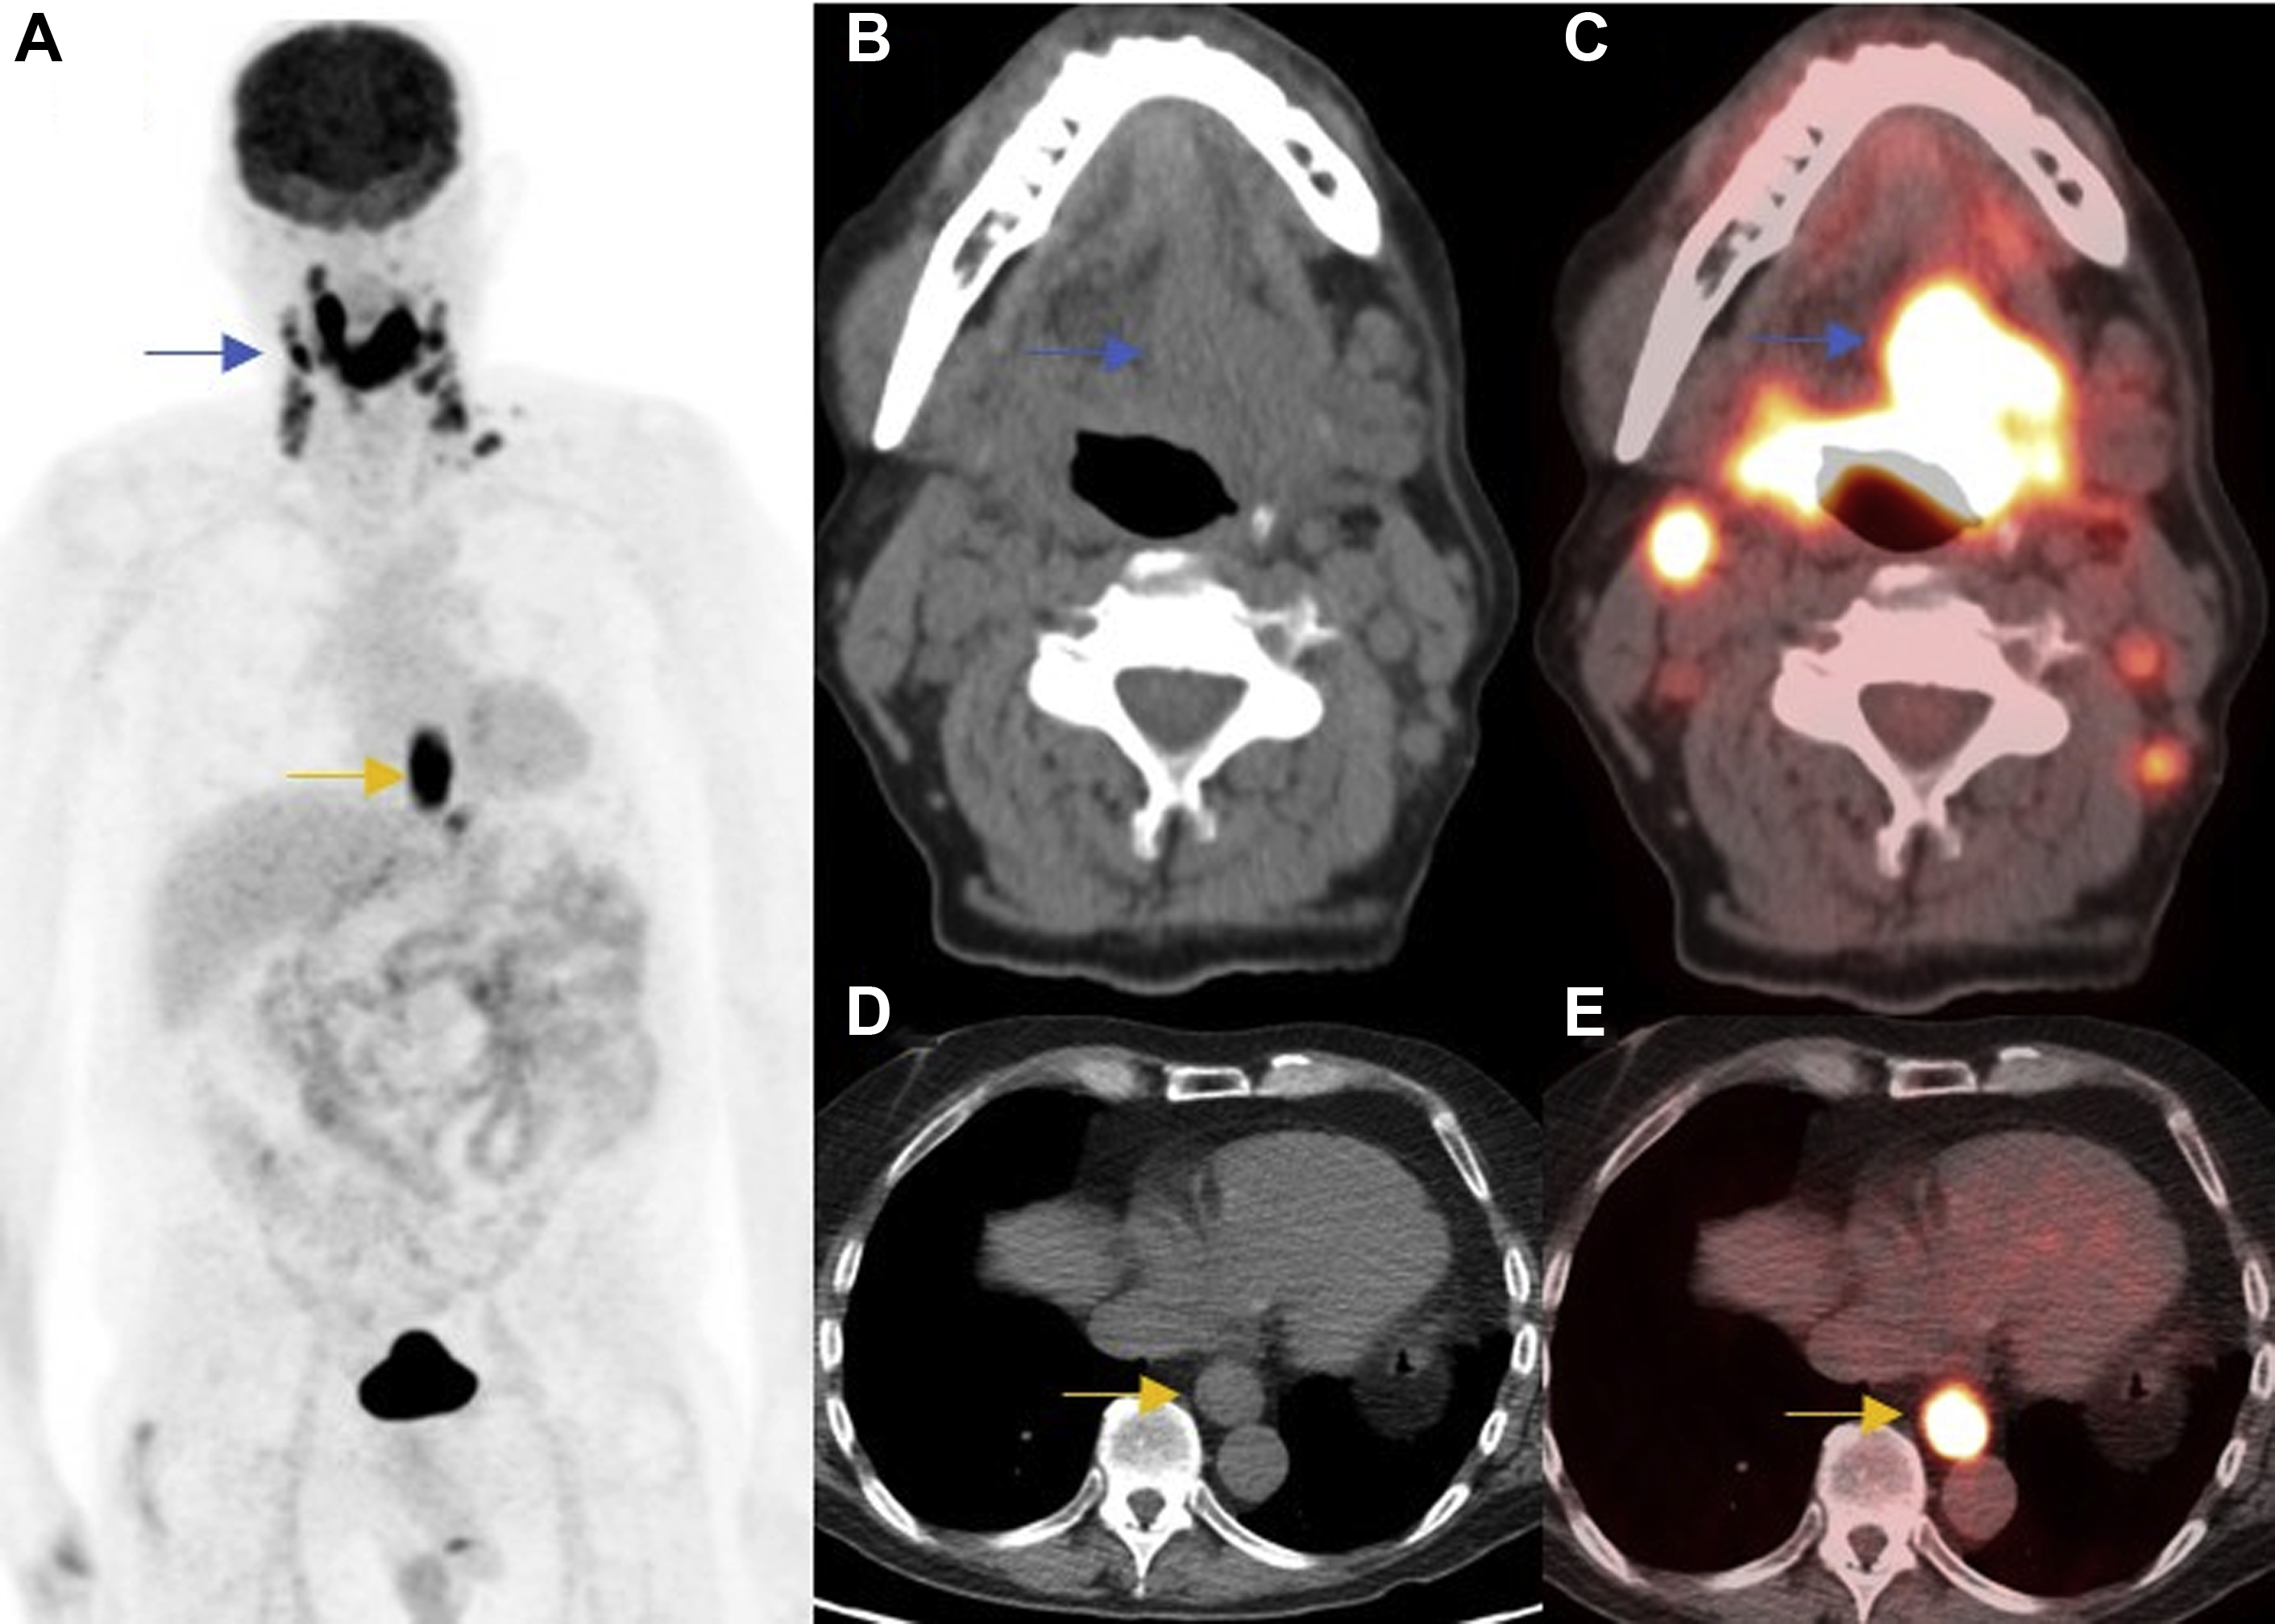

PET/CT and PET/MR Imaging of the Posttreatment Head and Neck Radiology Key

From radiologykey.com

PET/CT and PET/MR Imaging of the Posttreatment Head and Neck Radiology Key Pet The Head Pet head is the brand that helps create bounding love between you and your dog. We carry a large selection and the top brands like pet head and. Our fruity grooming ranges, fit any dog’s coat and nose which includes soothing shampoos, nourishing conditioners, hydrating sprays, soft. The test accurately details the size, shape, and function of. Natural ingredients and. Pet The Head.

PET/CT and PET/MR Imaging of the Posttreatment Head and Neck Radiology Key Pet The Head Our fruity grooming ranges, fit any dog’s coat and nose which includes soothing shampoos, nourishing conditioners, hydrating sprays, soft. A deodorising range suitable for all dogs and everyday use. Discover a wide range of premium pet head grooming products for your furry friends. Shop chewy for low prices and the best the company of animals pet head! The test accurately. Pet The Head.

PET/CT and PET/MR Imaging of the Posttreatment Head and Neck Radiology Key Pet The Head Find pet head sensitive soul dog spray deodorant for dogs with sensitive skin 10.1 fl. Pet head is the brand that helps create bounding love between you and your dog. Natural ingredients and vegan deodorizing spray. A deodorising range suitable for all dogs and everyday use. A brain positron emission tomography (pet) scan is an imaging test that allows doctors. Pet The Head.

PET/CT and PET/MR Imaging of the Posttreatment Head and Neck Radiology Key Pet The Head Natural ingredients and vegan deodorizing spray. Pet head is the brand that helps create bounding love between you and your dog. From potential injury to misunderstood signals, there are numerous factors to consider when it comes to petting a dog in the right way. We carry a large selection and the top brands like pet head and. A deodorising range. Pet The Head.